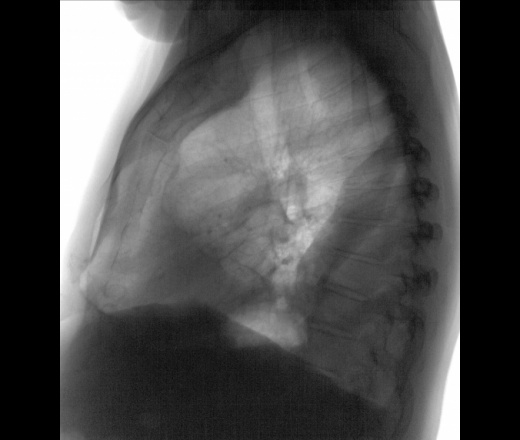

Мужчина 65 лет. Диагностическая флг. Коллеги, кто может сталкивался, впервые вижу, прямоугольная тень вдоль позвоночника на боковом снимке и в среднем отделе слева в прямой проекции.

Если диагностическая  флюорография, то какой диагноз предполагали? Какие клинико- лабораторные данные? Можно предложить осумкованнный паракостальный плеврит, по задней и передним грудым стенкам. Не исключается инфильтрация лёгочной ткани в переднем отделе (S5).

Как вариант к осумкованному паракостальному, рассмотрел бы вариант ателектаза нижней доли с осумкованным междолевым плевритом. В переднем синусе жидкость или липома. С генезом надо разбираться, пневмонический или обтурационный. Желательна клиника.